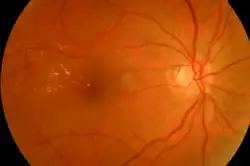

Drusen associated with aging and macular degeneration are distinct from another clinical entity, optic disc drusen, which is present on the optic nerve head.[2] Both age-related drusen and optic disc drusen can be observed by ophthalmoscopy. Optical coherence tomography scans of the orbits or head, calcification at the head of the optic nerve without change in size of globe strongly suggests drusen in a middle-age or elderly patient.